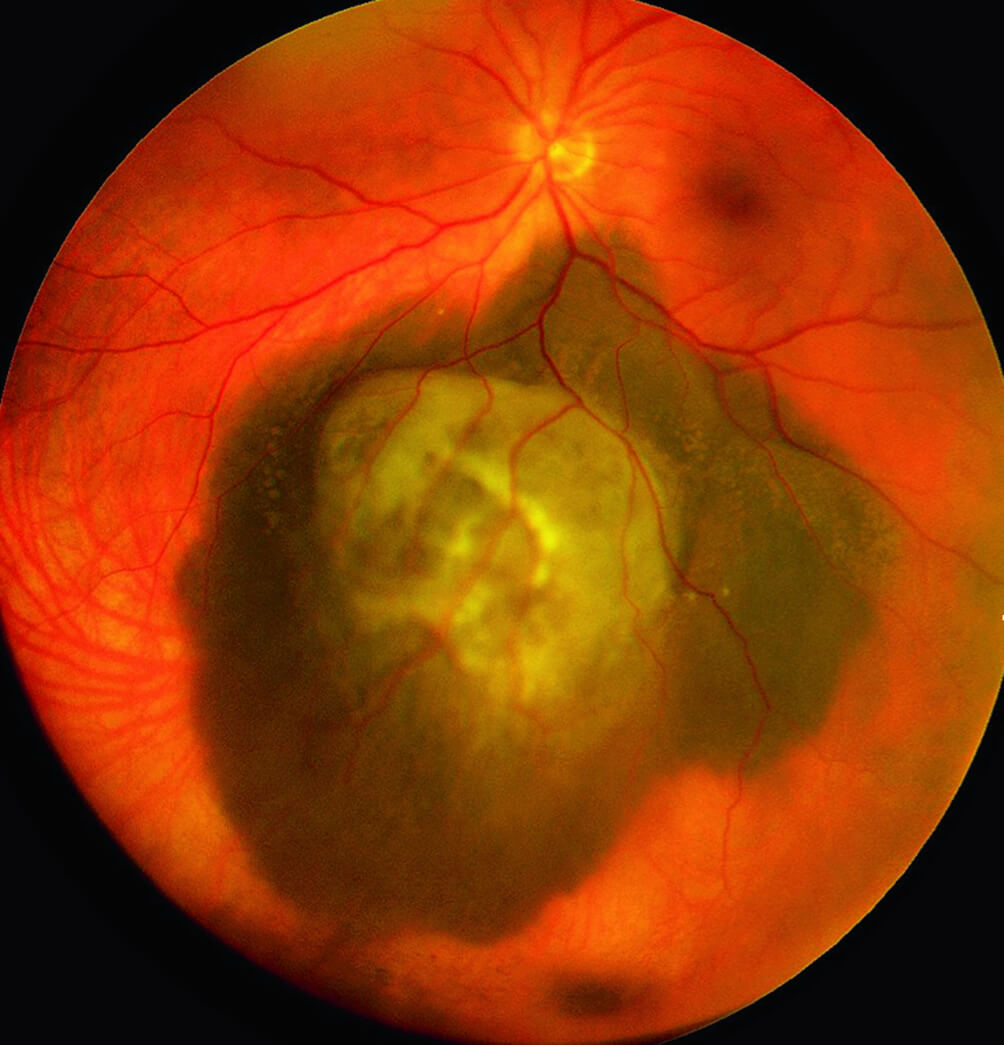

Атрофия зрительного нерва Лебера: Симптомы и лечение